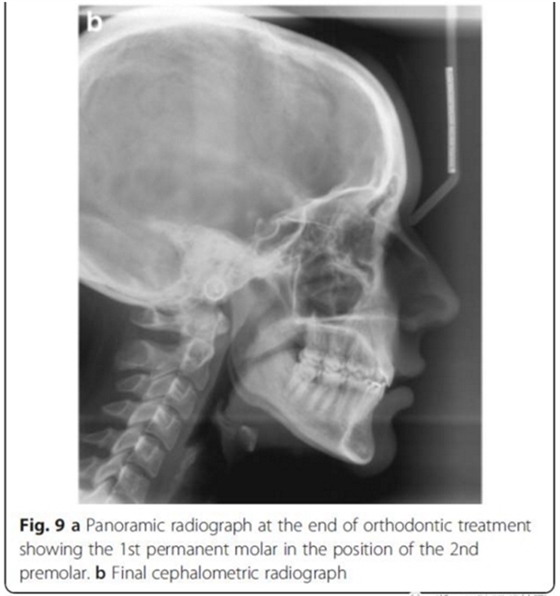

頭側(cè)分析,骨性I類關(guān)系,高角型

雙側(cè)I類尖牙和磨牙關(guān)系;完全的間隙關(guān)閉(用牙線確定);覆合覆蓋糾正;仍有輕度的中線偏離。頭測分析顯示,下切牙未發(fā)生舌側(cè)移動。